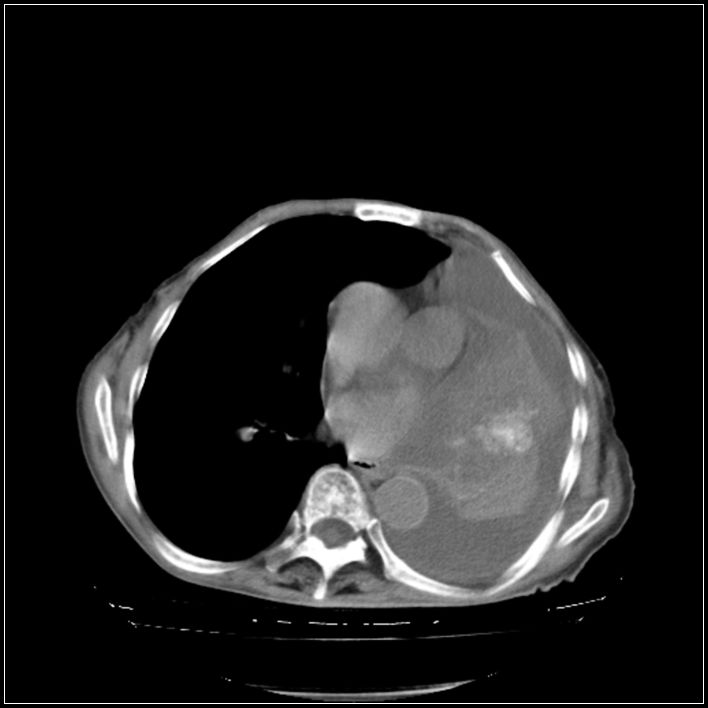

以下是引用影象小辈在2008-5-31 16:25:00的发言:[br]左侧胸腔团状不规则致密影,界欠规整,密度不均匀,其内可见更低密度影及高密度影,并可见包裹性胸腔积液 考虑为1.畸胎瘤 2.肺癌